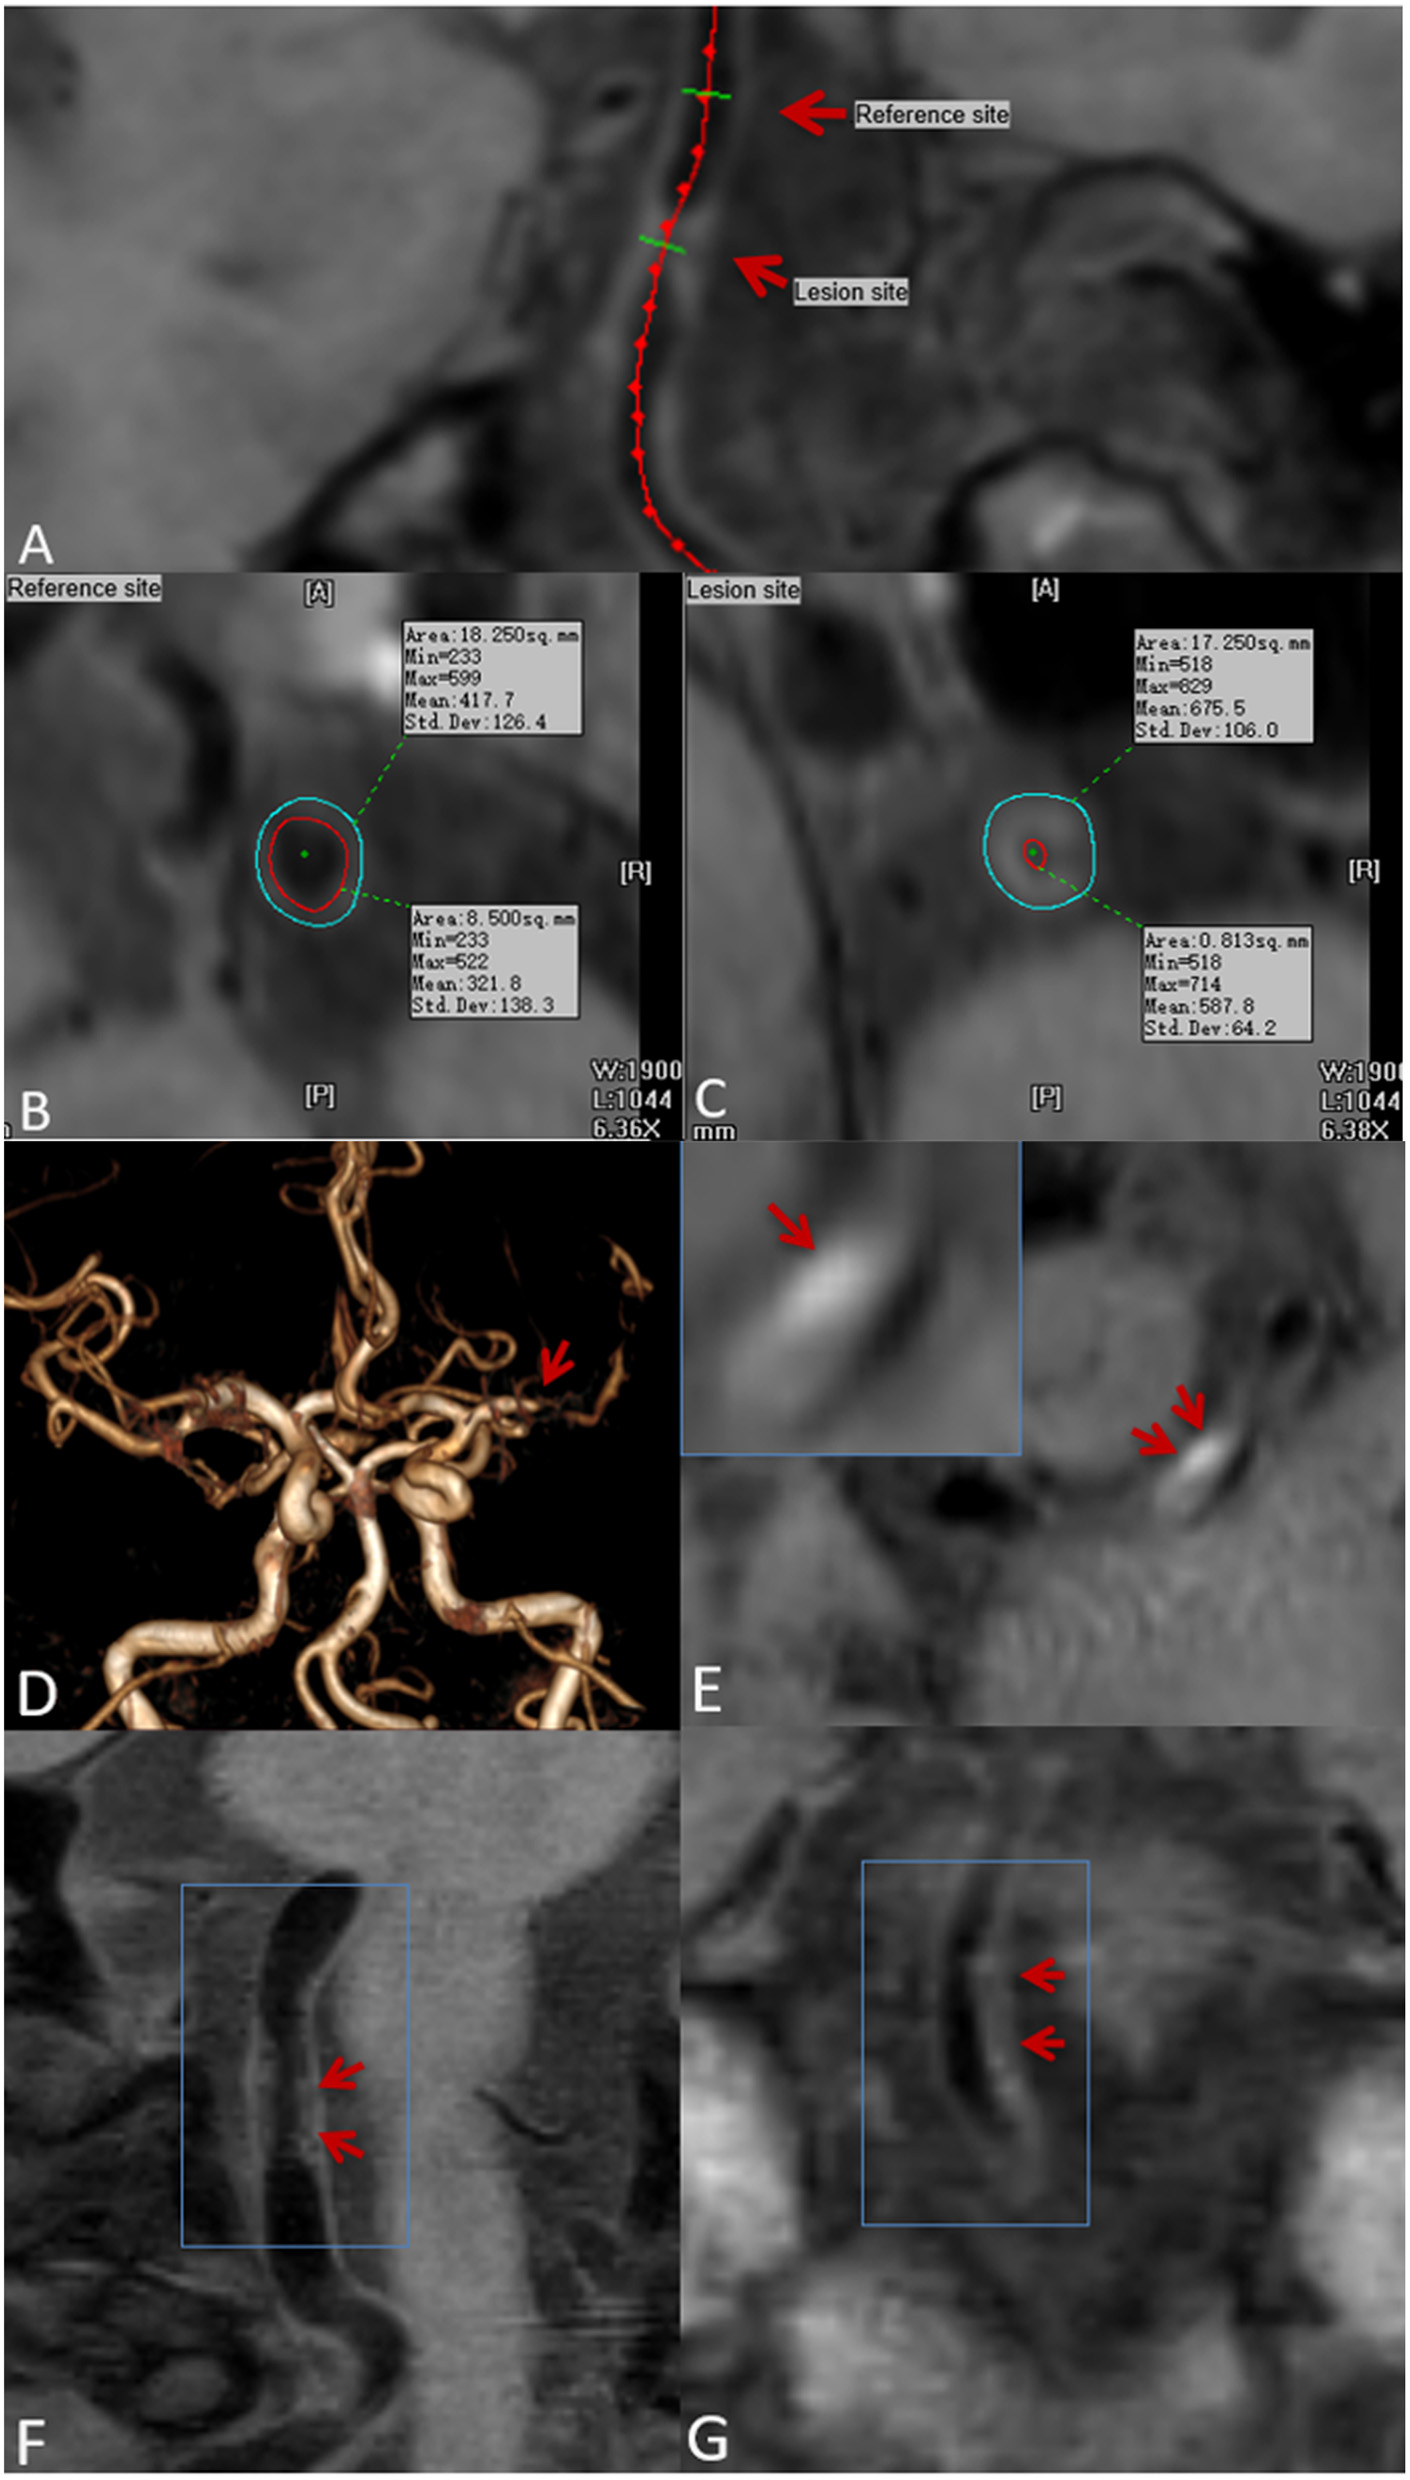

Figure 1

Plaque localization, composition, and surface morphology recognition. Ts-imaging software was used to perform curved planar reconstruction for the vascular axis. (A) (red arrow) with the thinnest wall as the reference site (B) and the thickest cross-section of the plaque as the lesion site (C). Lumen area (LA) and outer wall area (OWA) were calculated automatically by the software. Time-of-flight magnetic resonance angiography (TOF-MRA) showing stenosis of the M1 segment of the left middle cerebral artery (D) (red arrow): pre-contrast CMR vessel wall imaging shows an eccentric plaque at the stenosis, and a high-signal shadow can be seen in the plaque (E) (red arrow), indicating intraplaque hemorrhage. Plaque surface irregularity (F), and regularity (G) (red arrow).

Stenosis rate was defined as (1 – lesion LA/reference LA) × 100% (22). The mean values measured by the two reviewers was used for the subsequent analysis. With regard to T1 hyperintensity components, a high plaque signal was detected on T1WI, which was considered positive for intraplaque hemorrhage (23). A high signal intensity was defined as an area with an adjacent muscle signal intensity of >150% (Figures 1D,E) (24). The remodeling ratio (RR) was defined as OWA at plaque/OWA at reference. Three remodeling categories were defined as previously described: positive (outward expansion of the wall), RR > 1.05; intermediate, 0.95 ≤ RR ≤ 1.05; and negative (vessel wall shrinkage), RR < 0.95 (25). Regarding plaque surface morphology, an irregularity was defined as discontinuity at the plaque juxta luminal surface (Figure 1F) or smooth regularity at the plaque inner wall (Figure 1G) (22). Intracranial plaque enhancement was classified into three grades on post-contrast T1-VISTA images: grade 0, no enhancement, defined as the degree of enhancement similar to that of normal vessel wall; grade 1, defined as the degree of enhancement less than that of the pituitary infundibulum but greater than that of normal vessel wall; and grade 2, defined as the degree of enhancement similar to or greater than that of the pituitary infundibulum (Figure 2). For inconsistent cases, another senior neuroradiologist (with 10 years of experience in imaging-based diagnosis) reassessed images and assisted in reaching a consensus.